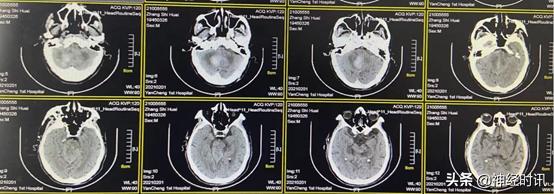

3月4日(脑血疏用药6周后)复查CT,显示患者小脑血肿已完全吸收,患者病情明显好转

4月7日(出院1月后)复查CT,显示患者小脑、脑干及脑室系统均已恢复正常